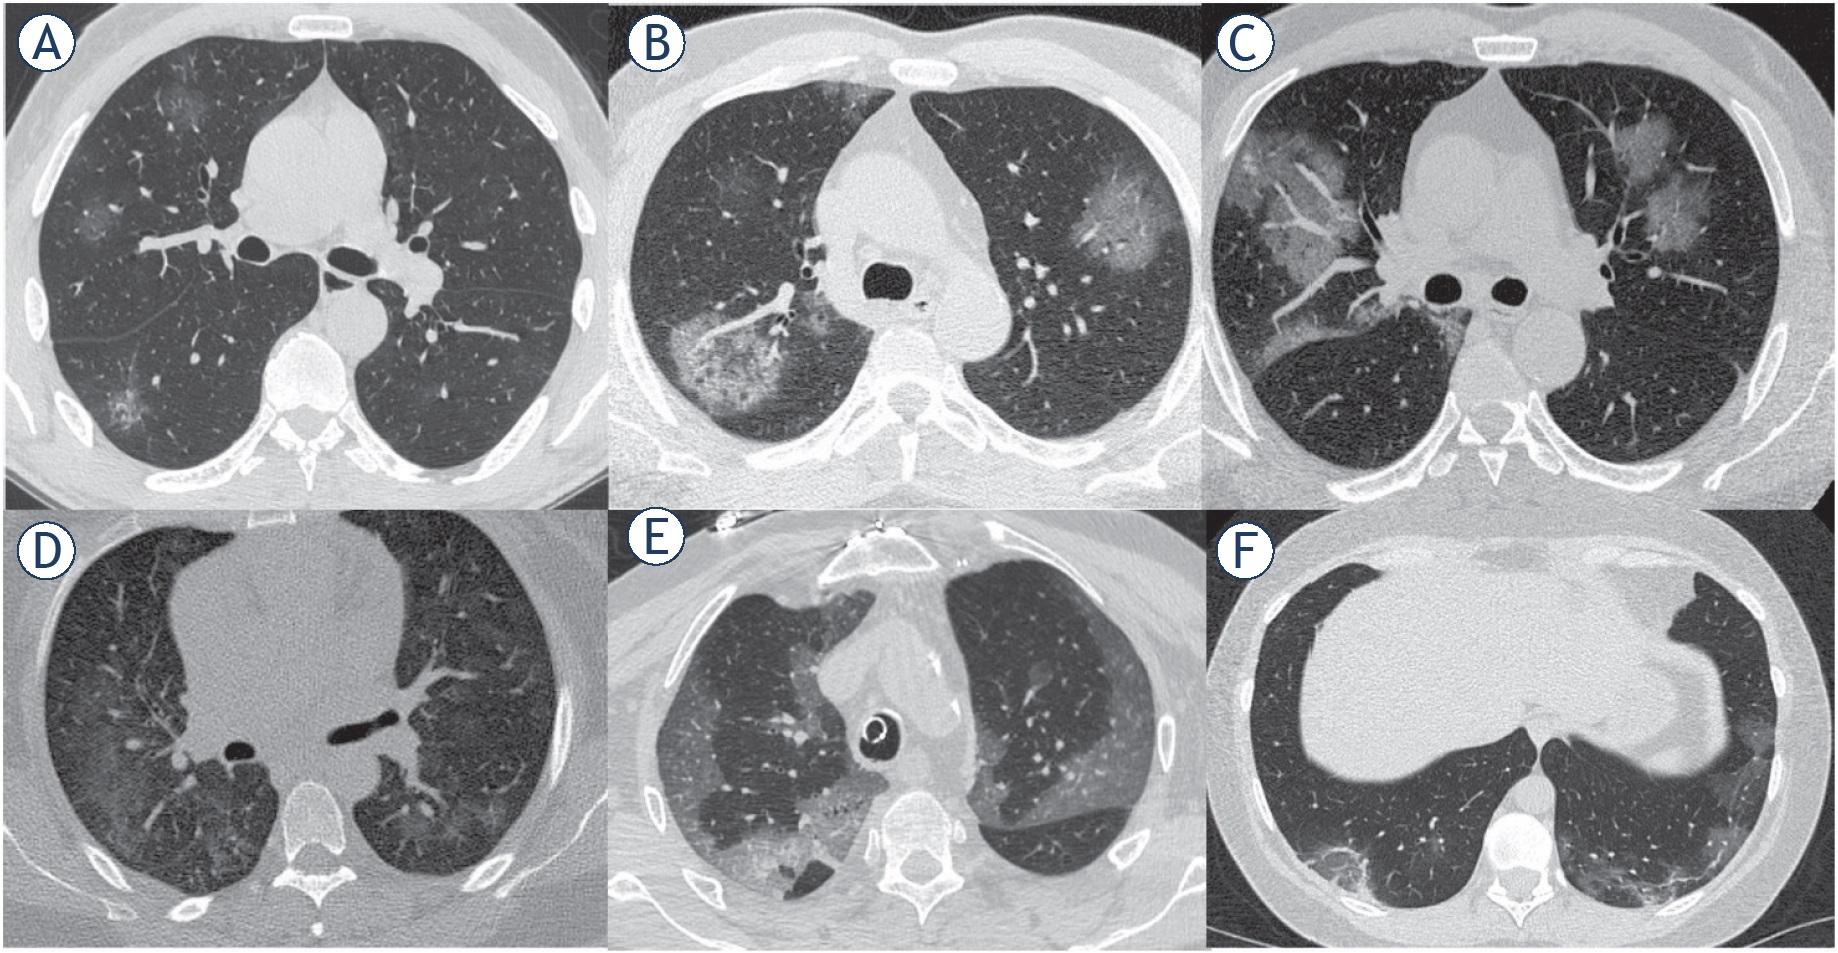

Man, 61 year. CT shows ground-glass opacities separated by thickened interlobular septa. (A-F) Axial planes.

Early stage. One-three days after clinical manifestations. “CT scan shows single or multiple scattered patchy or agglomerated ground-glass opacities, separated by honeycomb-like or grid-like thickened of interlobular septa” 7 – crazy paving (Figure 3).